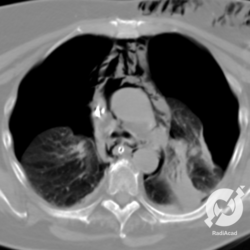

Aqui temos uma tomografia de um paciente com DPOC caracterizada pela presença de enfisema centrolobular, estas pequenas imagens hipoatenuantes (escurinhas) sem paredes definidas, espalhadas pelo parênquima. Além do enfisema, podemos perceber nas regiões subpleurais, periféricas, algumas imagens gasosas que são bolhas enfisematosas, mais acentuadas à direita, bem como imagens de enfisema centrolobular. Não é tão frequente uma bolha de enfisema determinar um pneumotórax (arredondando, de 1:1000), mas existe um substrato pra desencadear pneumotórax. Neste caso em questão ele é pequeno, à direita, um pneumotórax espontâneo secundário.